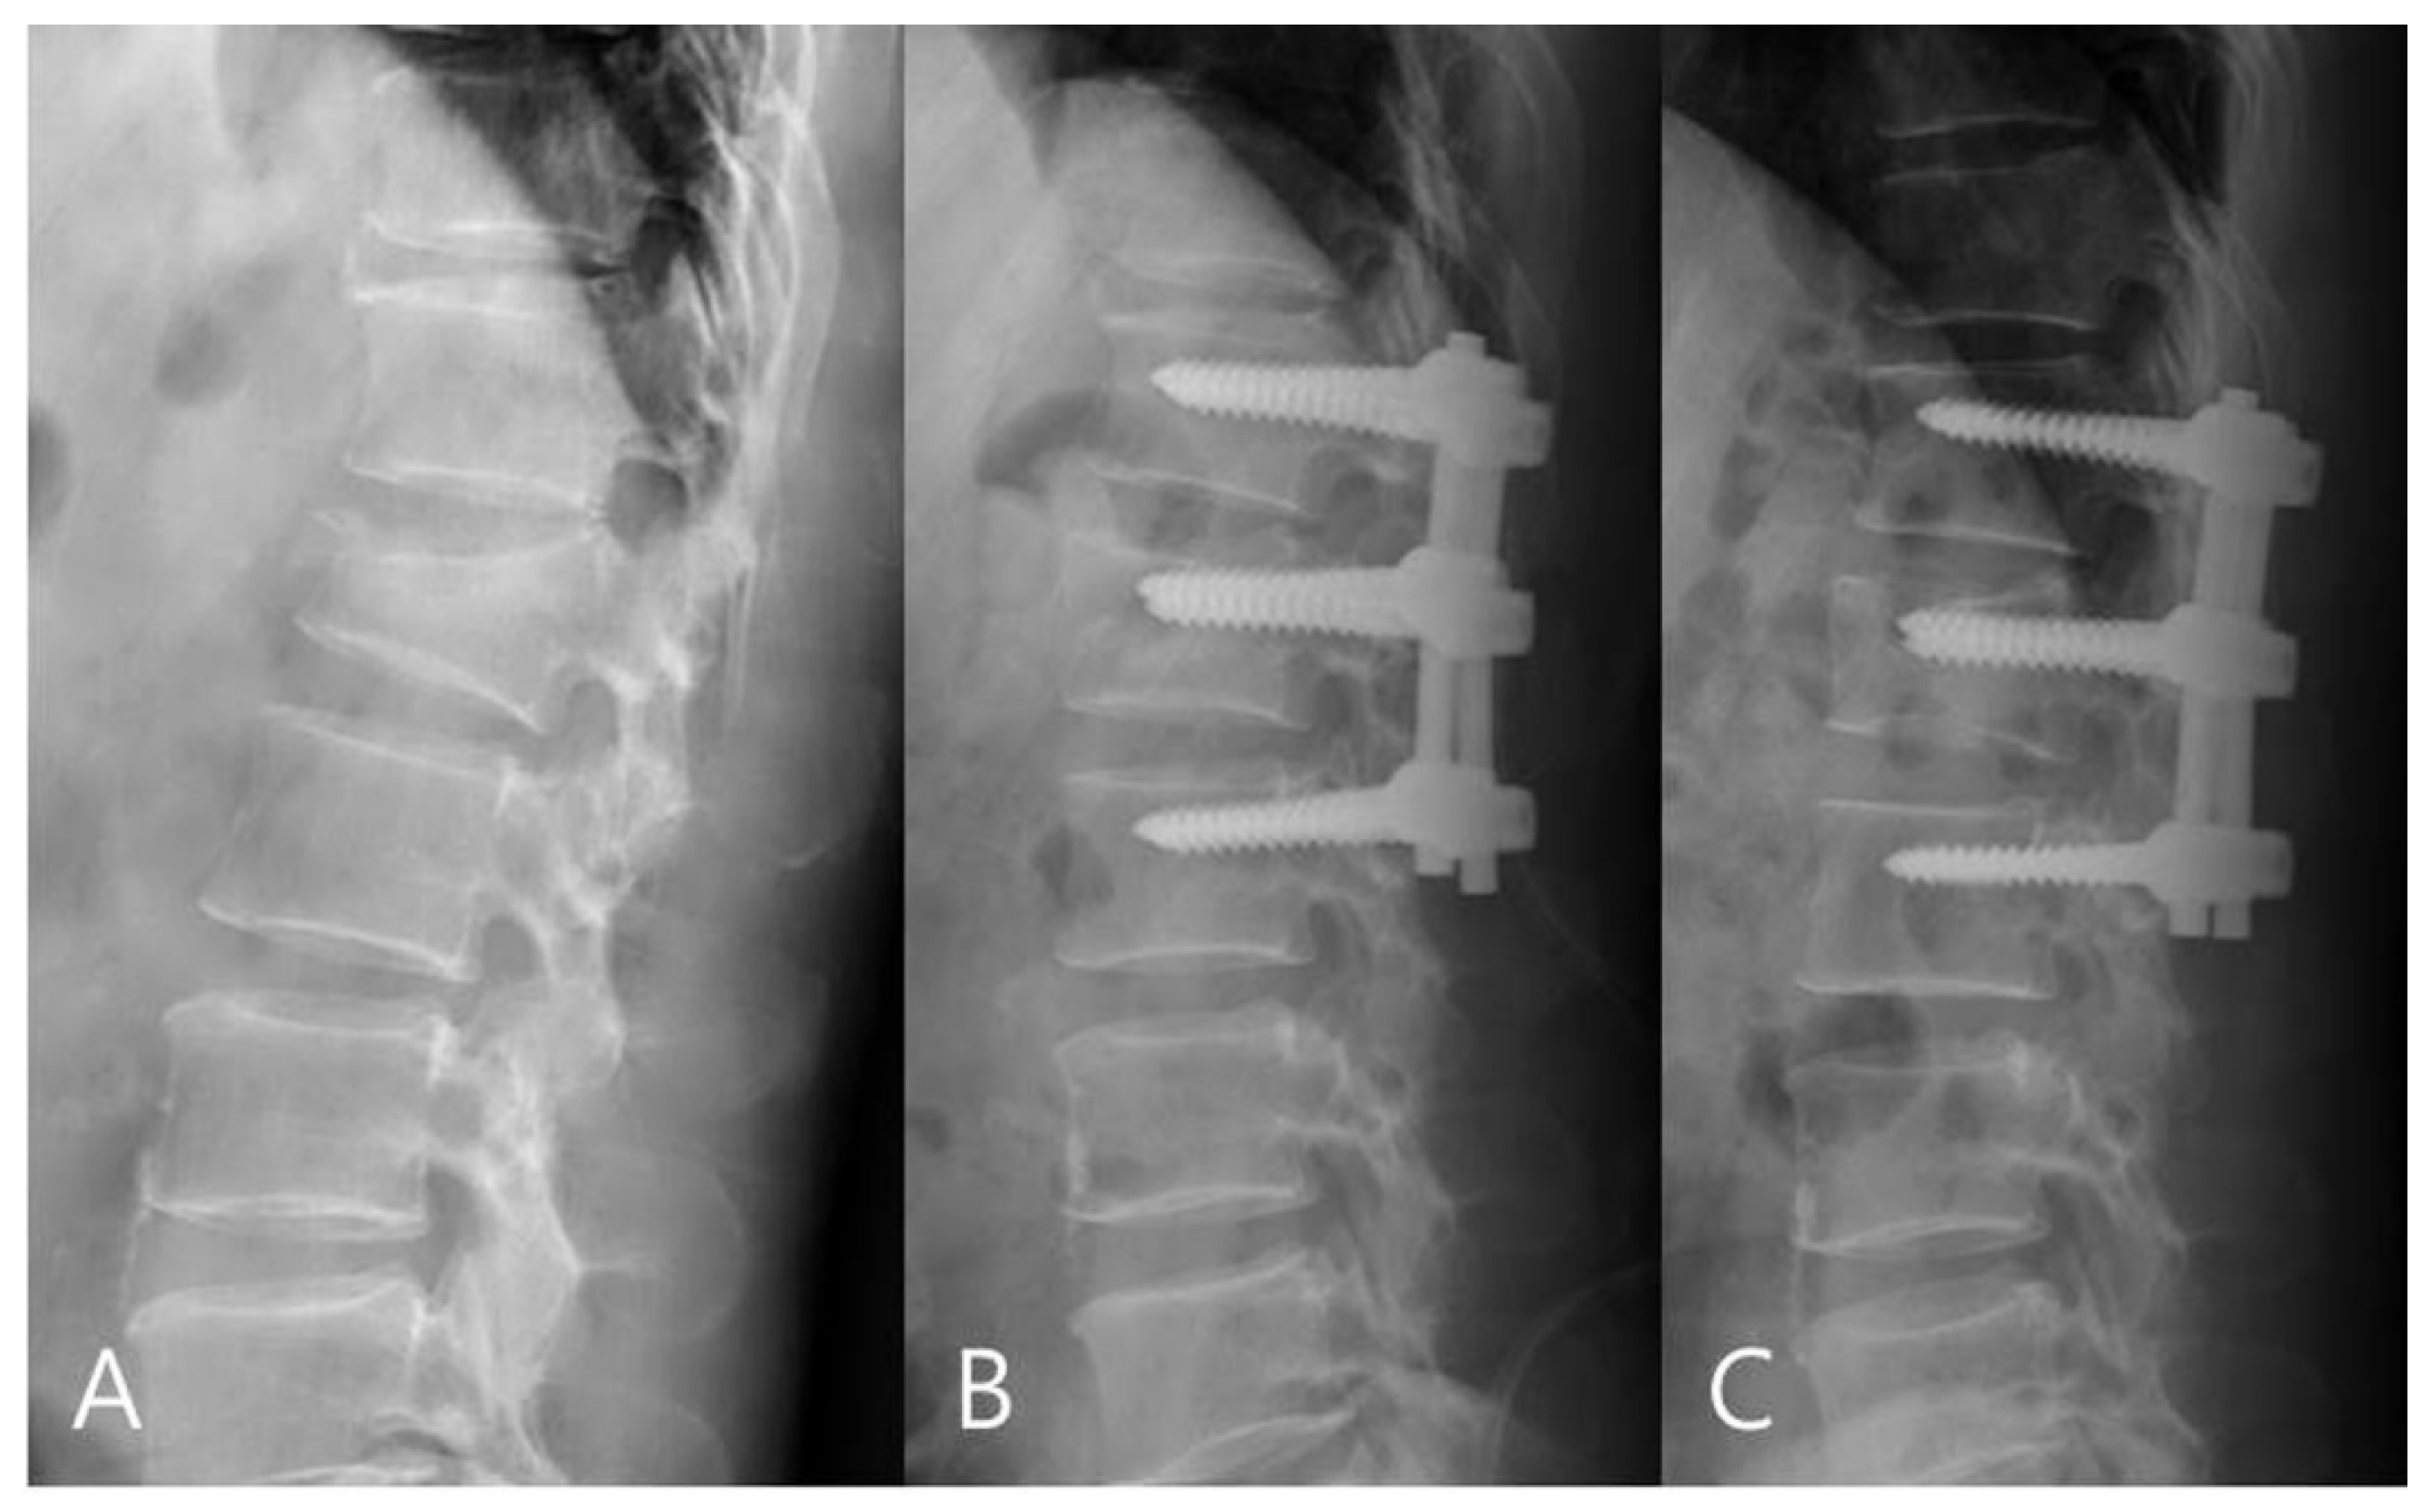

For the mono group, the preoperative mean RKA was 21.56°, and the postoperative mean RKA was 8.13°. The mean correction angle was 13.43° (correction rate 62.31%). The RKA angle decreased from 8.13° to 11.18° (correction loss: 14.18%) in late follow-up. For the poly group, the preoperative mean RKA was 23.18°, and the postoperative mean sagittal plane kyphosis was 11.09°. The mean correction angle was 12.09° (correction rate 52.17%).The RKA decreased from 11.09° to 18.83° (correction loss: 33.42%) in late follow-up. The mono-axial pedicle screw fixation had a better correction rate and reduced the risks of correction loss versus the poly-axial pedicle screw fixation (Figure 3 and Figure 4).

Figure 3.

(A) 58-year-old male patient with L1 burst fracture was treated by mono-axial pedicle screw fixation. (B) Postoperative and (C) final follow-up imaging show good correction and no correction loss.

Figure 4.

(A) 45-year-old male patient with L1 burst fracture was treated by poly-axial pedicle screw fixation. (B) Postoperative imaging showed a mild correction of anterior body height and kyphosis. (C) Final follow-up imaging showed correction loss.